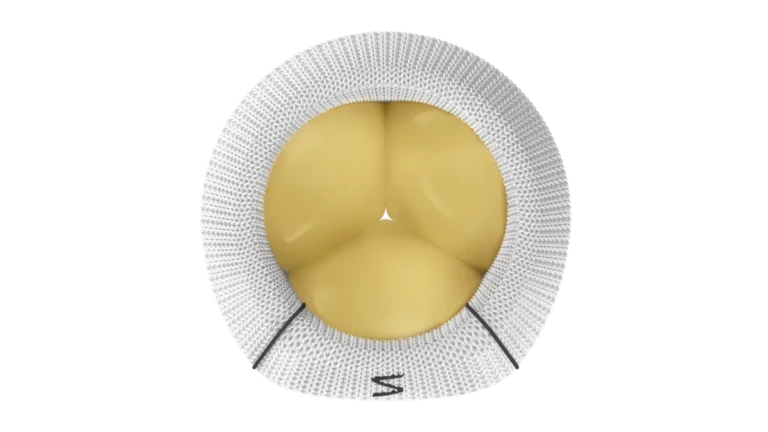

فناوری نوین «عصبزدایی لگنچه کلیه»؛ رویکردی جدید برای درمان هدفمند فشار خون بالا شرکت وِرو مِدیکال (Verve Medical) با معرفی فناوری نوآورانه «عصبزدایی لگنچه کلیه» (Renal Pelvic Denervation یا RPD)، گام تازهای در درمان بیماران مبتلا به فشار خون کنترلنشده برداشته است؛ رویکردی که میتواند رقابت جدیدی را در بازار درمانهای مداخلهای فشار خون…